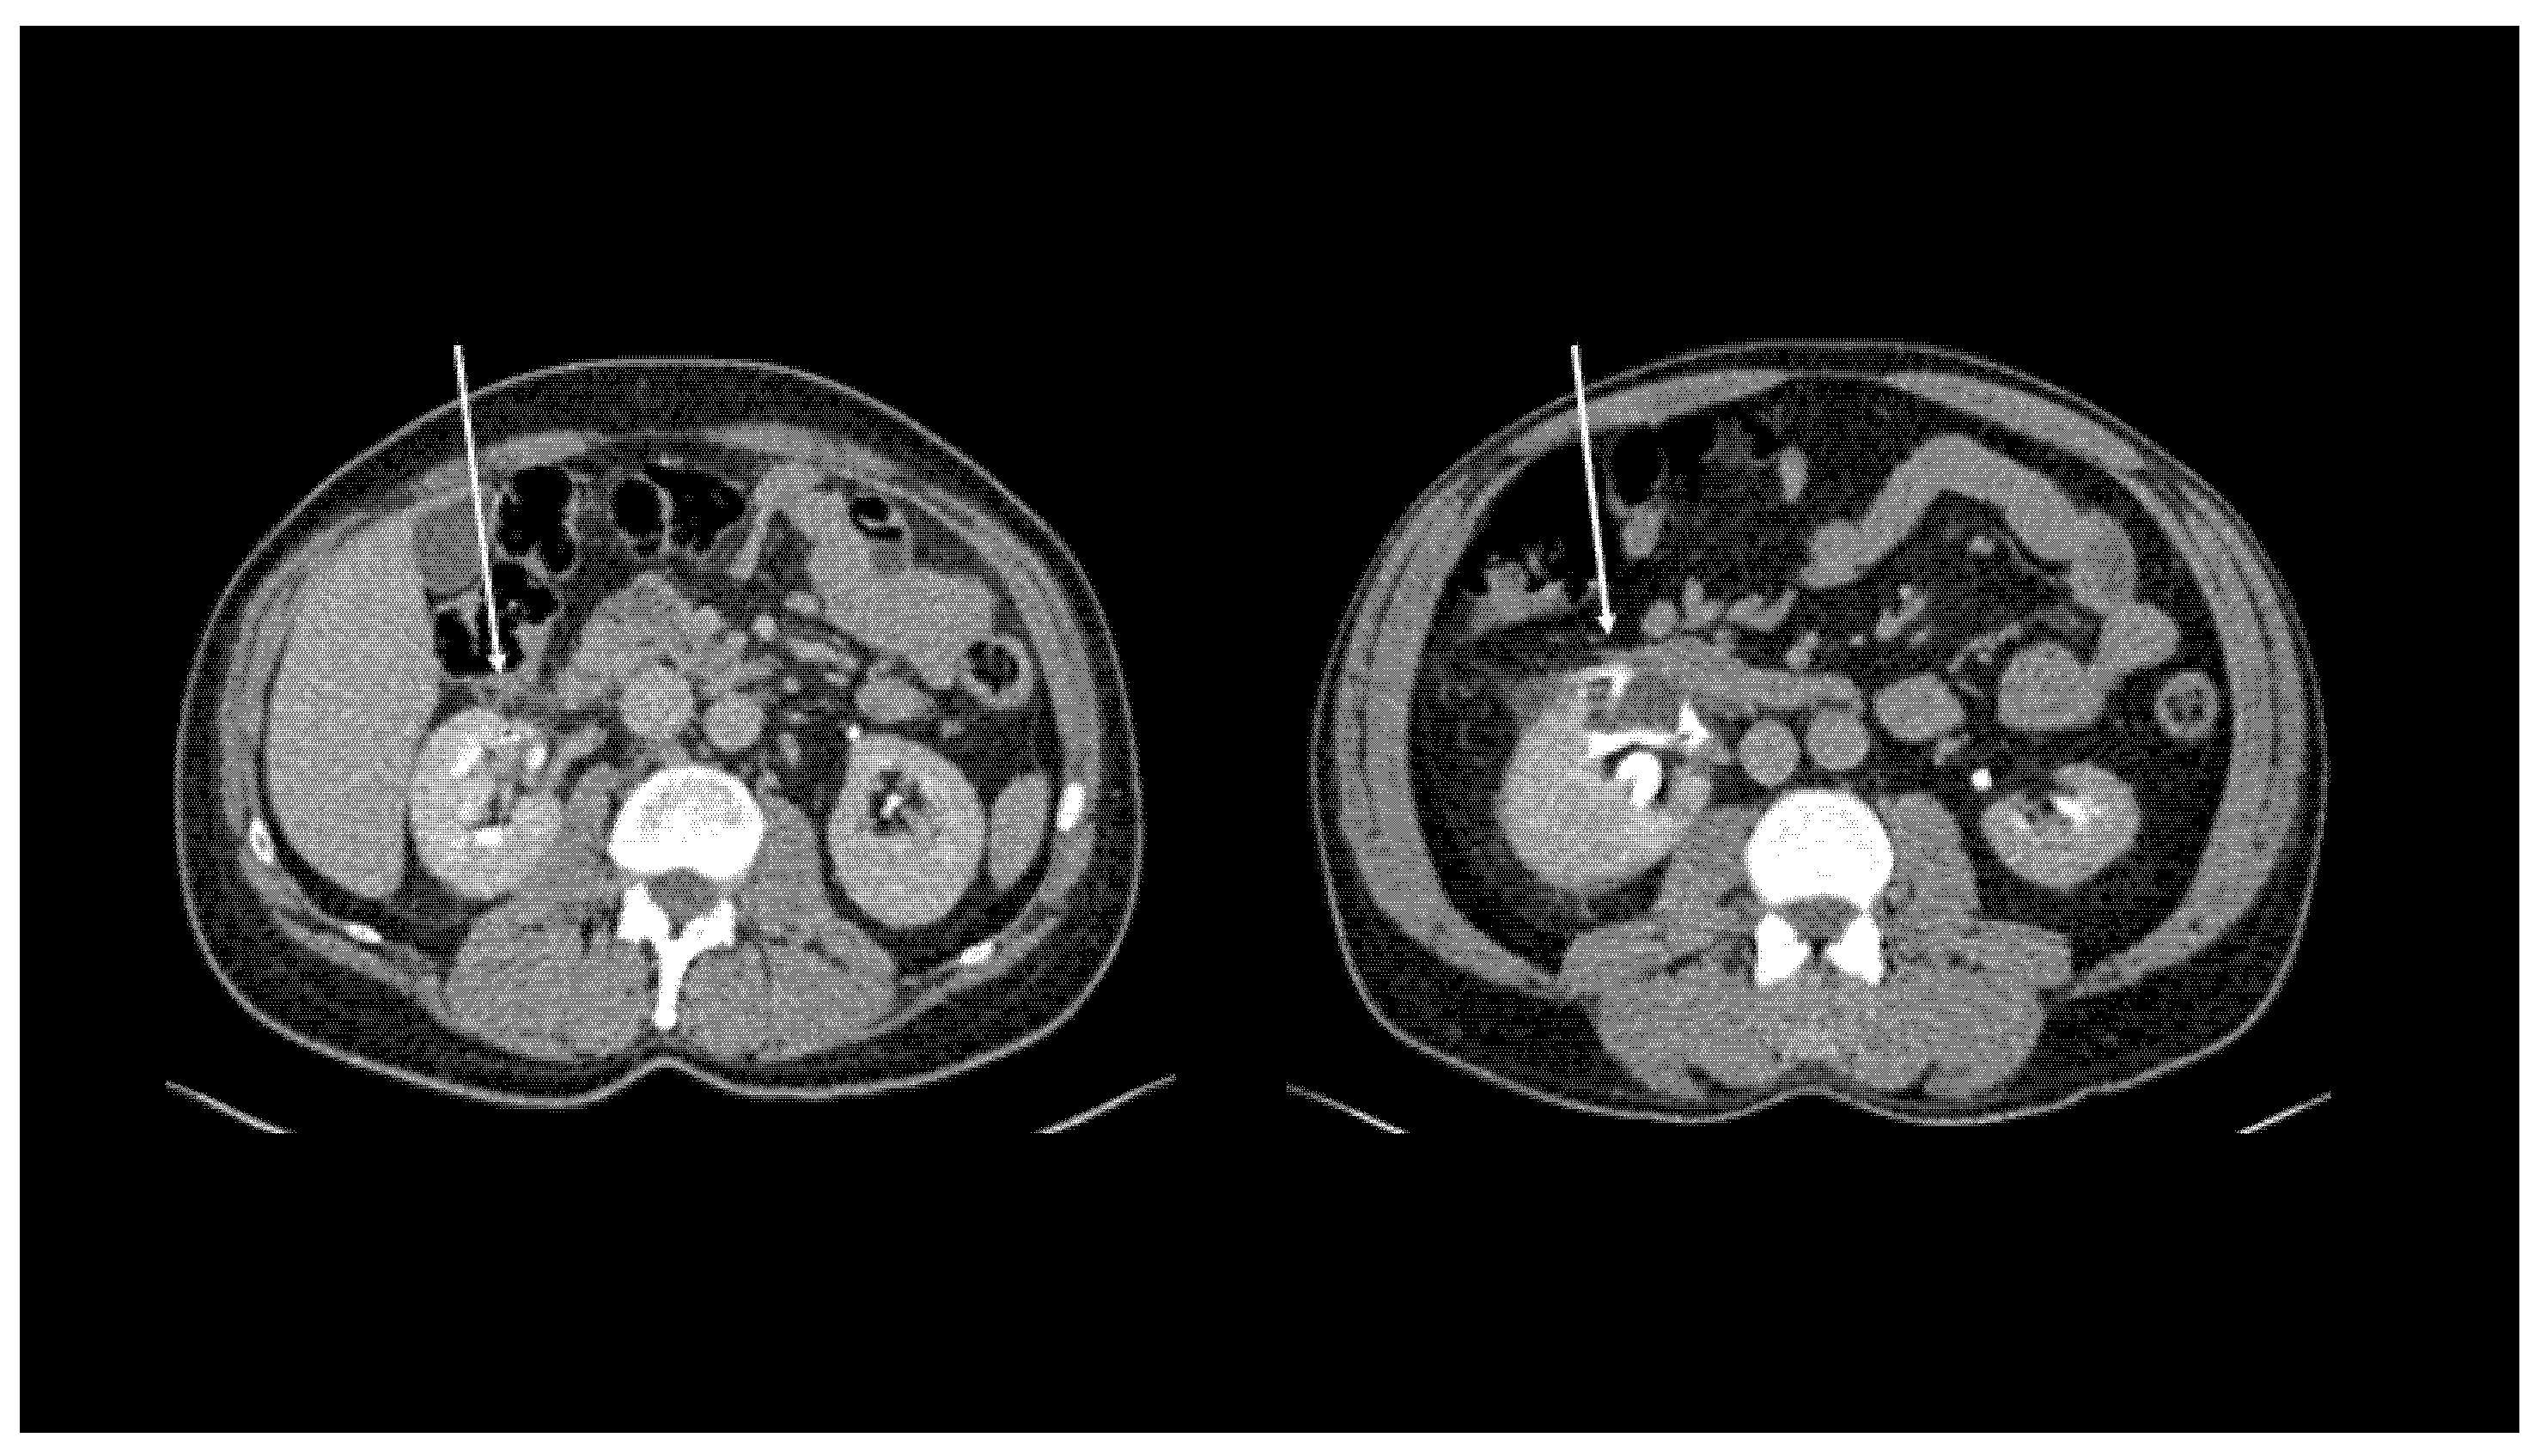

| Local spread | 24 (36.4%) | 27 (40.9%) | 26 (39.4%) |

| Free Fluid | 39 (59.1%) | 36 (54.5%) | 35 (53.0%) |

| Urinoma | 3 (4.5%) | 3 (4.5%) | 5 (7.6%) |

| Cohen’s Kappa | 0.74 * | 0.72 *; 0,70 § | |

| ICC (95% CI) | 0.88 (0.81–0.93) * | 0.87 (0.79–0.92) *; 0.86 (0.78–0.92) § |

| Local spread vs. | 5.1, (1.54–10.17) | <0.01 | 4.5, (1.35–8.14) | 0.01 |

| Free fluid/Urinoma |